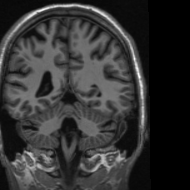

4.3 Medical Image Compressive Sensing

Medical image compressive sensing is an everlasting practical application in image reconstruction area. In this section we test the performance of the proposed ResGD-Net on compressive sensing reconstruction of brain MR images [3] (CS-MRI). In CS-MRI problem, the data fidelity term is , where , is a binary selection matrix representating the sampling trajectory, and is the discrete Fourier transform. We randomly pick images from the brain MRI datasets [3], then crop and keep the central part with less background. Then we at random divide the dataset to images for training and for testing. Among this section, we present the comparison results between ResGD-Net and ISTA-Net+ [33], where the latter one is a state-of-the-art method in tackling with CS-MRI problem. For fairness, both algorithms compared here are evaluated on the same dataset and metrics. Experiments are conducted across different sampling ratios , and of to show the generality. The study of ResGD-Net on different sampling ratios and various phase numbers is shown in Fig. 4. The PSNR comparison with ISTA-Net+ is shown in Table. 2. The result enhancement of the proposed ResGD-Net against ISTA-Net+ is remarkable across all sampling ratios even though we only use approximately many number of parameters than ISTA-Net+ [33].

In addition, we provide the visualization results of some selected MR images reconstructed by the state-of-the-art ISTA-Net+ [33] and our proposed ResGD-Net on compressive sensing (CS) ratio , and . The results are evaluated under metrics the Peak Signal-to-Noise Ratio (PSNR), the Structural Similarity (SSIM) and the Mean Squared Error (MSE). For better visualization, we rescale the pixel value by multiplying on the error maps (the second row of Figs. 5 - 7) when displaying.

PSNR: dB

SSIM:

MSE:

PSNR: dB

SSIM:

MSE:

PSNR: dB

SSIM:

MSE:

PSNR: dB

SSIM:

MSE:

PSNR: dB

SSIM:

MSE:

PSNR: dB

SSIM:

MSE: